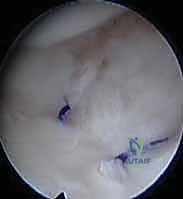

المركب الغضروفي الليفي الثلاثي (TFCC) وأهميته القصوى

يُعد المركب الغضروفي الليفي الثلاثي (Triangular Fibrocartilage Complex - TFCC) بمثابة "غضروف الركبة" بالنسبة للمعصم. إنه هيكل معقد يتكون من أربطة وغضاريف تربط المفصل الزندي الكعبري البعيد بعظام الرسغ.

* وظيفة الـ TFCC: يوفر استقرارًا حيويًا للمفصل (DRUJ)، ويساعد في امتصاص الصدمات وتوزيع الأحمال الميكانيكية عبر المعصم أثناء رفع الأشياء الثقيلة أو الاستناد على اليد.

* الارتباط بالناتئ الإبري: ترتبط العديد من أربطة الـ TFCC مباشرة بالناتئ الإبري للزند (Ulnar Styloid). لذلك، فإن أي كسر في قاعدة الناتئ الإبري غالبًا ما يصاحبه تمزق في هذا المركب الغضروفي، مما يؤدي إلى عدم استقرار شديد في المعصم يستوجب تدخلًا جراحيًا دقيقًا، وهو ما يبرع فيه الأستاذ الدكتور محمد هطيف باستخدام تقنيات المناظير (Arthroscopy).